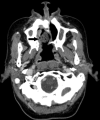

Fig 7.

A 69-year-old patient with SCC of the right maxilla status post subtotal maxillectomy. An axial postcontrast CT image shows a hollow obturator (arrow) in place.